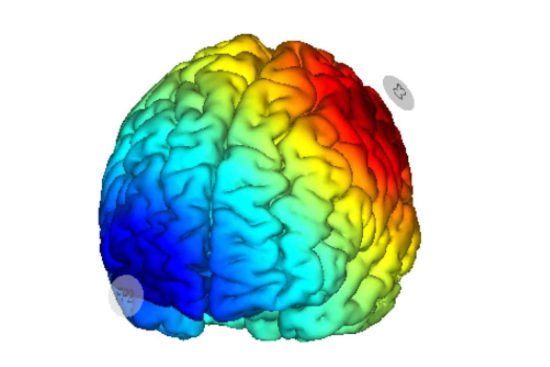

De esta manera, el flujo de corriente penetra en la corteza cerebral y produce un efecto modulador de la capacidad de excitación de las neuronas. En pacientes que padecen fibromialgia, esta terapia se dirige a áreas cerebrales relacionadas con el procesamiento del dolor. De esta manera, es posible obtener efectos analgésicos prolongados, disminuyendo tanto el dolor como la frecuencia de episodios críticos.

En cuanto al procedimiento, en cada sesión se coloca un casco con electrodos incorporados en la cabeza del paciente. Después, se aplica una corriente eléctrica de muy baja amplitud durante un período de entre 20 y 30 minutos.